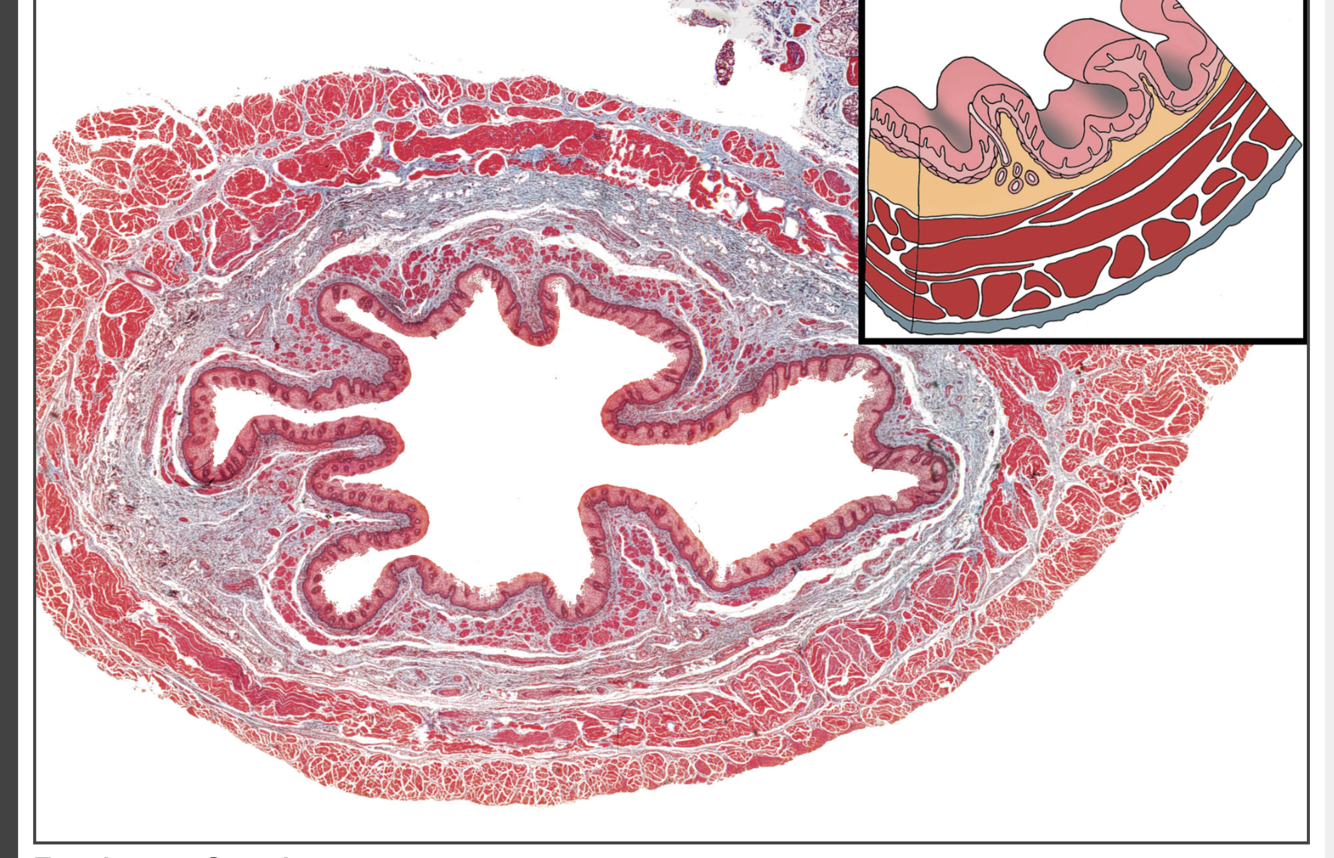

59

What is this

Pancreas - can see the ducts and cal also see the lighter bits are the islets of langerhans